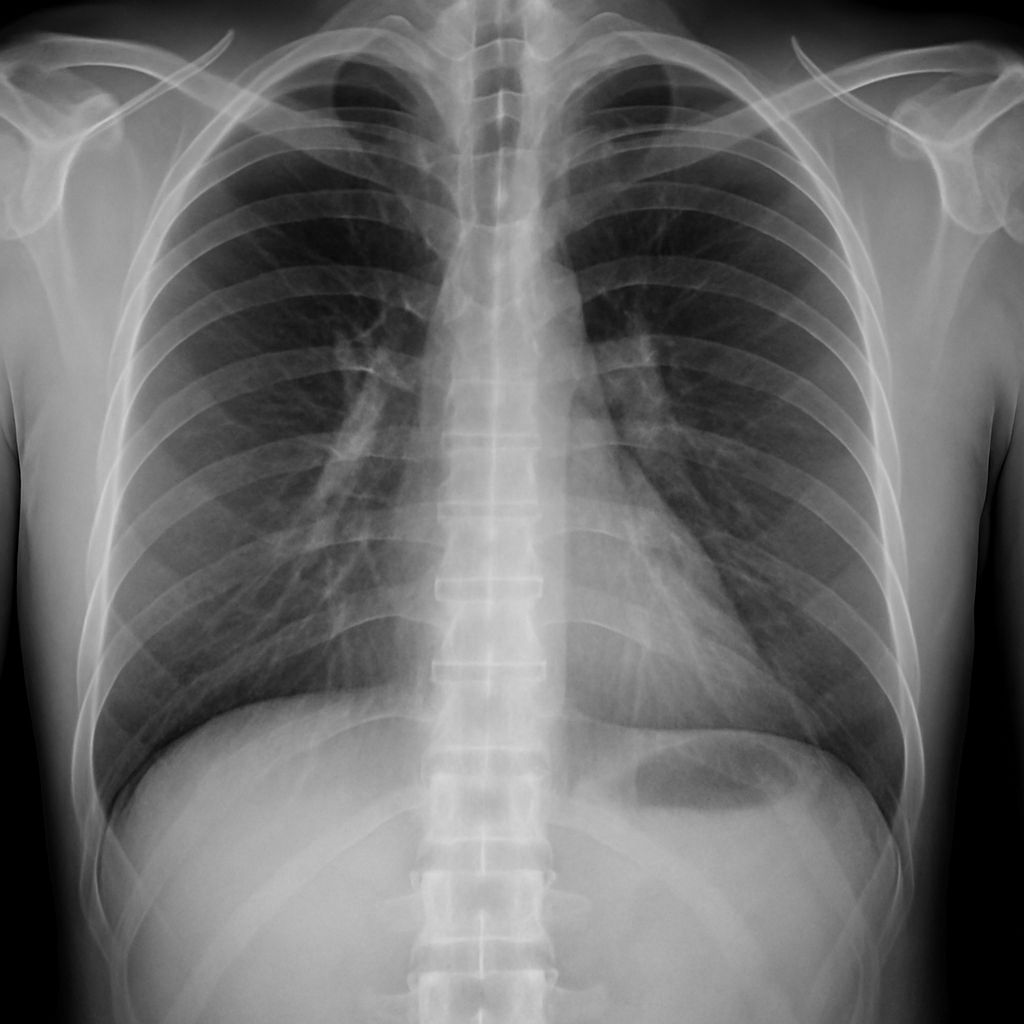

Lunit’s Insight CXR AI suite for chest x-ray imaging analysis was used by the Saudi government and the country’s Seha Virtual Hospital to identify respiratory disease among Hajj pilgrims.

The company’s system helped healthcare teams analyze chest x-rays for infectious diseases such as tuberculosis, pneumonia, and Middle East Respiratory Syndrome (MERS).